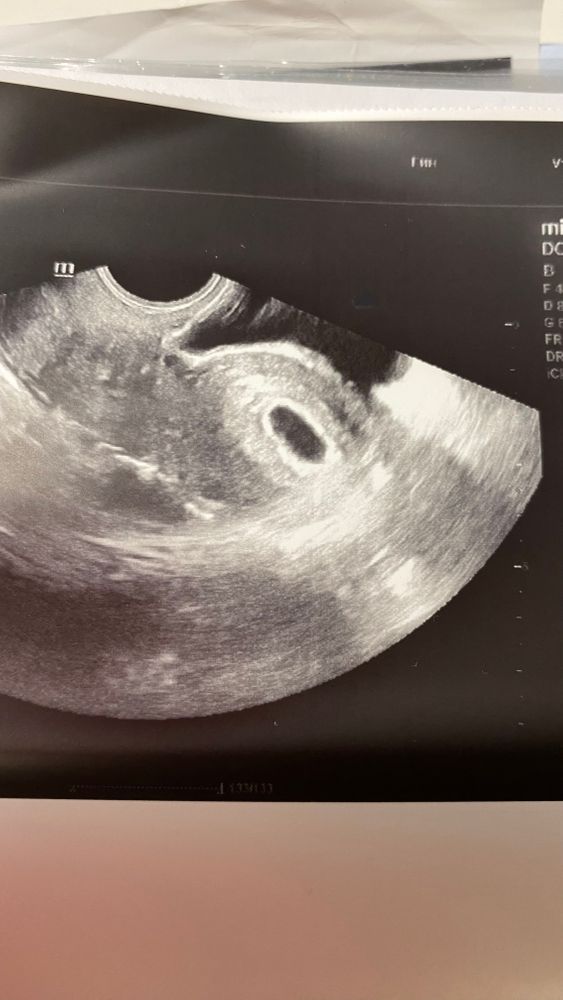

21 дпп УЗИ нет жм

моя ре на больничном. Но она сказала сходить на УЗИ. ПЯ нашли 15-17 мм

сб еще не прослушивается, но это и понятно. Рано.

а вот то, что нет жм меня смущает, хотя она и не искала.

поставила беременность 4-5 недель.

Повтор узи через 4-5 дней. Но на картинке вроде что-то просеивается

С таким размером ПЯ точно уже жм должен быть. Просто не описал наверное узист его.

Кристина Белякова, мне кажется в верху жм. Мой ре на 19 дпп, тоже не чего не сказал про жм, сама потом на фотографии увидела

Но как будто он есть😀